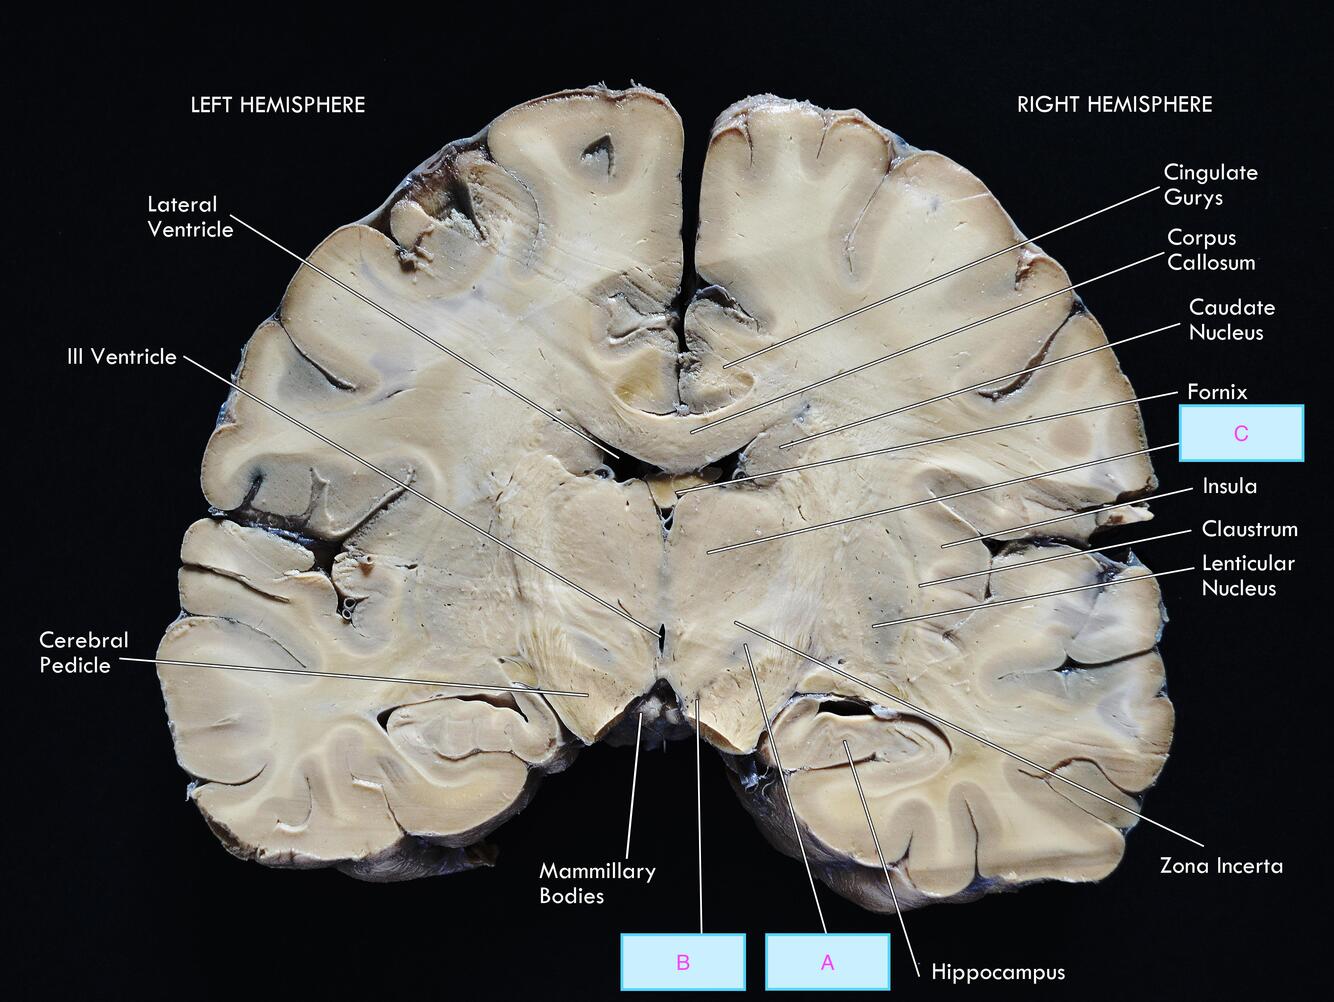

Label A-C [3]

A: subthalamic nuclei

B: substantia nigra

C: thalamus

(sub is on top)